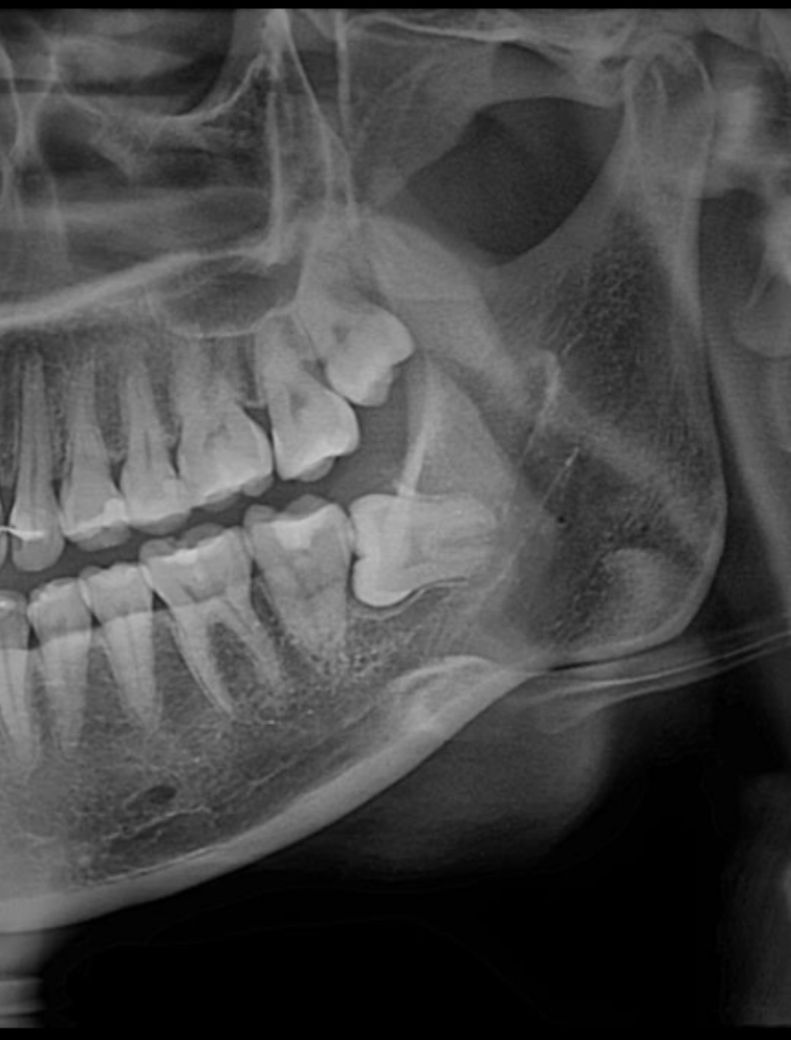

상악하악 발치예정인데 상악은 천공가능성 있나요..?

하악도신경가깝다고 하는데문제없이발치가능할지궁금하네요ㅠㅠ 그리고 마취하면 발치할때는정말안아픈가요

상악 발치는 난이도가 크게 어렵진 않지만 아래 치아는 신경과도 거리가 가깝고 매복 깊이도 깊어서 난이도가 좀 있어 보입니다.

1. 상악은 큰 문제는 없어보입니다

2. 하악은 ct찍어보면 더 정확할텐데 지금 파노엑스레이 상으론 약간 눌려있는것 같긴합니다 발치 시, 발치 후 소파 작업 시 주의해야하고 발치 후 주의사항도 꼭 잘 지켜야 합니다

3. 마취 충분히 합니다